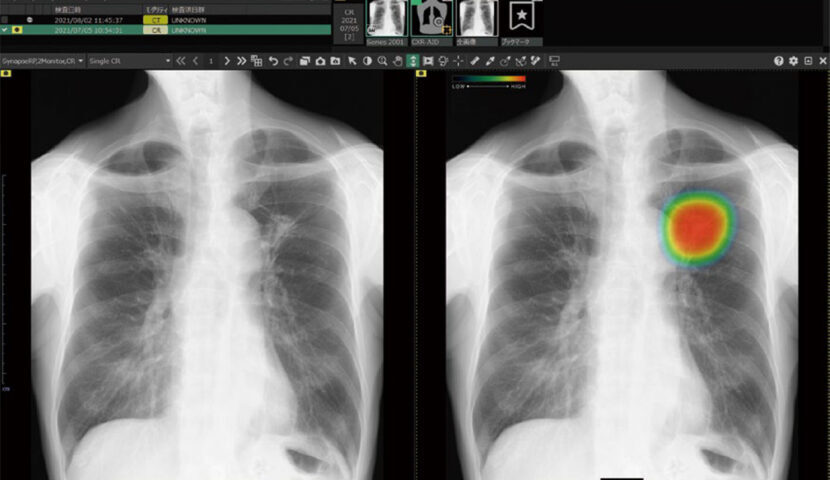

3. ヒートマップ表示機能: 異常が疑われる領域をAIが自動的に解析し、確信度に応じて色分けして表示します。

4. スコア表示機能: 確信度を0~100の数字で表示し、スコアの最大値が数値として表示され一目で診断の参考にできます。